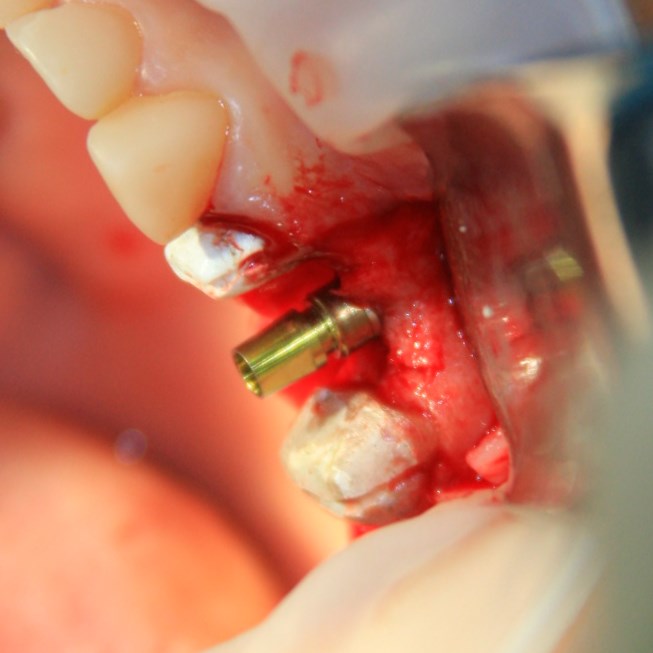

К установке имплантов можно приступать через 3-4 месяца (рис 52, 53):

Рисунок 52, 53. Установка импланта через 3 месяца после удаления зуба и синуслифтинга: слева – скелетирование верхней челюсти, справа – установленный имплантат.